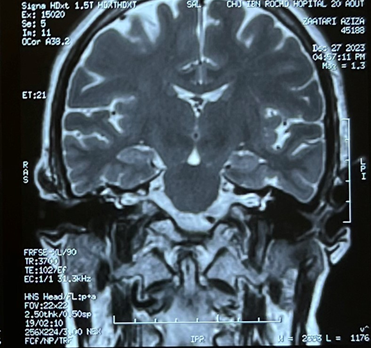

In the mr imaging of the temporal bone schowed

abnormal signal intensity within the right middle ear cavity which appeared

hypointense on t1-weighted, hyperintense on t2-weighted images with minimal

peripheral enhancement post-gadolinium, coincide with the diagnosis of

cholesteatoma. Mastoid cell filling are also filled in, with loss of the

annular appearance of the right semicircular canal (figure 5).

Figure 5: mr

imaging of the temporal bone schowed a loss of the annular appearance of the

right semicircular canal.